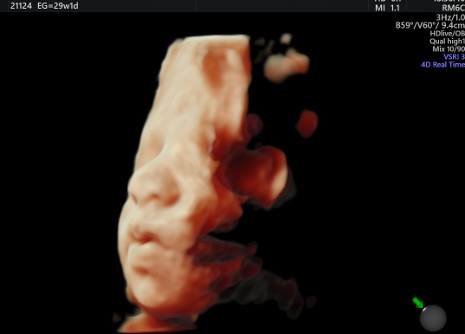

, cuenta con un ecógrafo de última generación Voluson E10 BT18, capaz de ofrecer imágenes de alta definición en 2D, 3D y 4D HD live Silhouette- HD liv estudio desde las primeras semanas de gestación y una excelente penetración para exámenes técnicamente difíciles tanto fetales como ginecológicos.

"Además, es importante destacar el factor emocional. Para las futuras madres ver la cara de sus hijos de forma tan definida consigue aumentar el vínculo madre-hijo desde mucho antes del nacimiento".